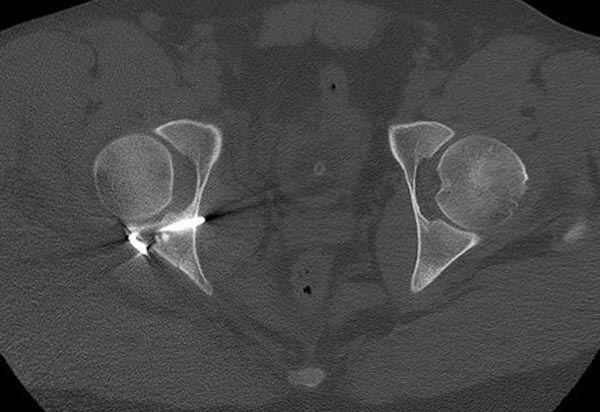

11:50 больной в послеоперационной, рентгенограмма N7, компьютерная томограмма в тот же день N8-10

5:24 Рентгенограмма таза, вызывают врача ортопеда (снимок N1), его диагноз: закрытый переломо-вывих правого тазабедренного сустава, получает добро на закрытую репозицию в приемном отделении

7:30 начало операции, больной на спине, попытка репозиции после анестезии N3, укладка больного на боку, доступ Kocher- Langenbeck, состояние седалищнего нерва около 2.5см кровоподтек, через joistick головка бедра приподнята, освобовождение сустава, фрагмент заднего края более 3х4 см репонирован на свое место. После промывания

сустава, репозиция вывиха (N4), фиксация фрагмента 2.7(4) мм шурупами и допольнительно реконструктивной пластиной на 8 дырок, фиксация 3.5мм шурупами проксимально и дистально.

Интраоперционные N5 косая запирательная и N6 подвздошный снимок